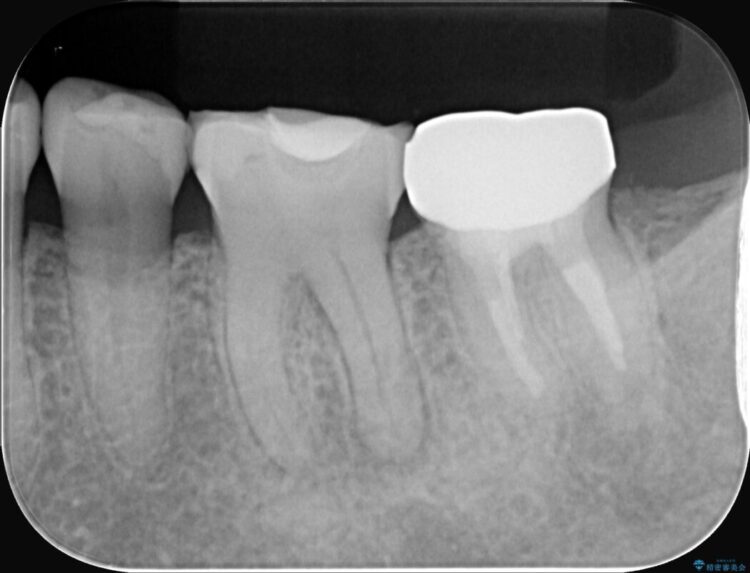

詰め物内部の虫歯治療、隠れた根管の発見

詰め物内部の虫歯治療、隠れた根管の発見 ビフォー 詰め物内部の虫歯治療、隠れた根管の発見 アフター

奥歯の詰め物が取れたとご来院された患者様です。